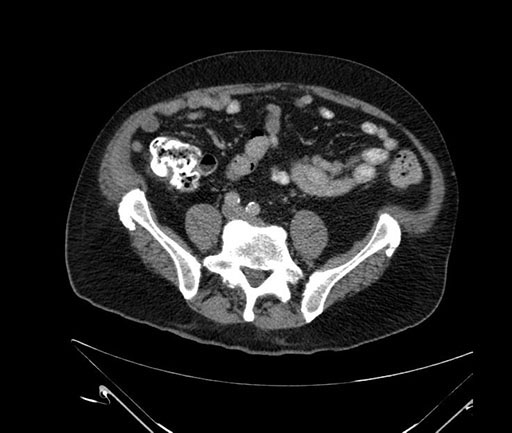

Whipple (pancreaticoduodenectomy) [case 7]

Axial - 3 months prior

Imaging analysis

Based on your CT findings, which issue(s) would give reason for "planned slowing down moment(s)" in this case?

Considering a standard Whipple procedure, what step(s) of the operation would you do differently in this case?